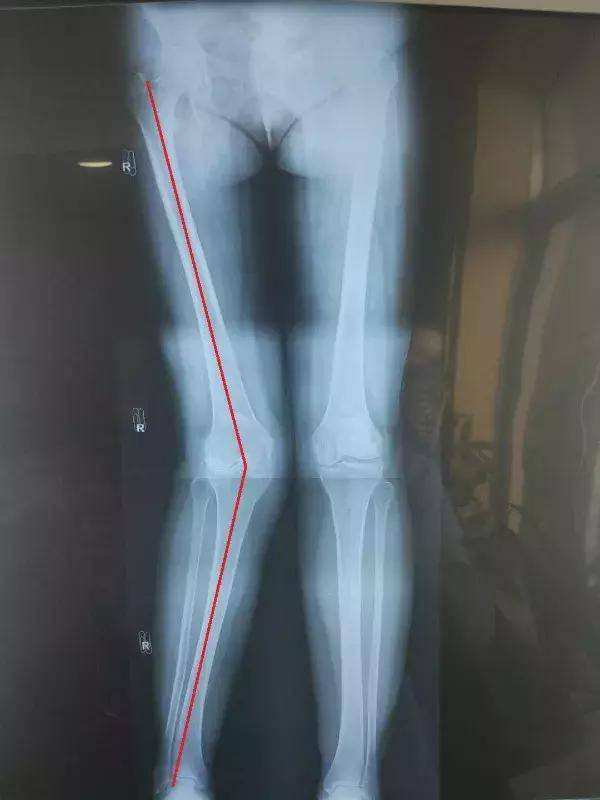

最准确的还是拍摄下肢全长片来判断

A.机械轴是一条绘制于站立式前后位双腿全长放射显影图上的线,此时骨盆处于水平位置,双髌骨朝前。连接股骨头和踝的中心位置,机械轴将水平的膝关节一分为二。

B.将膝分成四个象限,考虑到生理性差异机械轴应该穿过内侧或外侧1区。机械轴偏向进入2或3区是手术干预的指征。